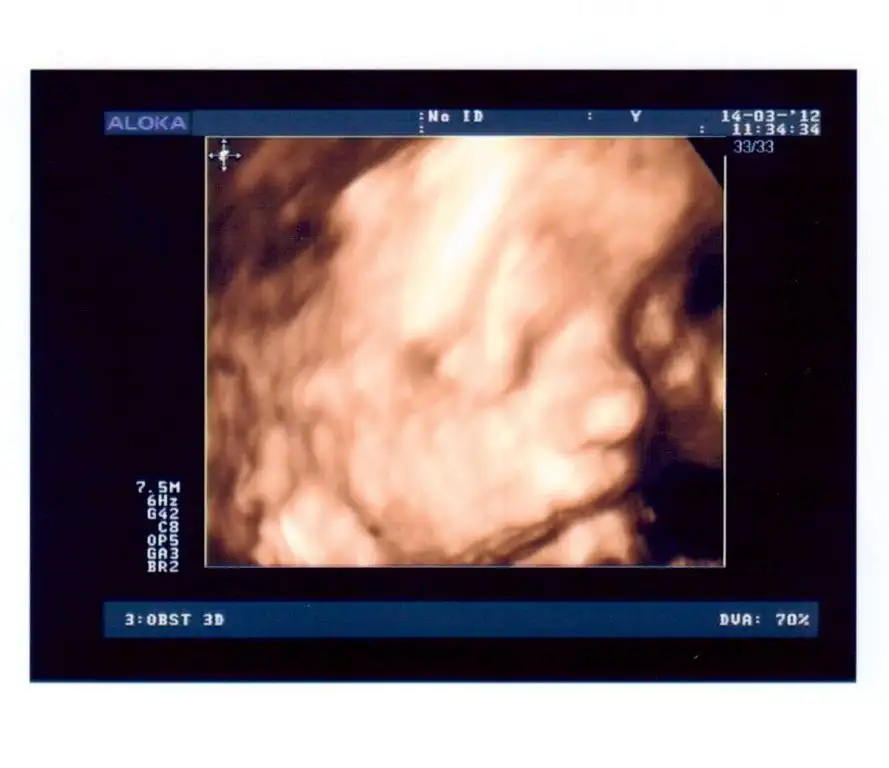

bende göbüşümün içindekini göstereyim

Eki Görüntüle 367414